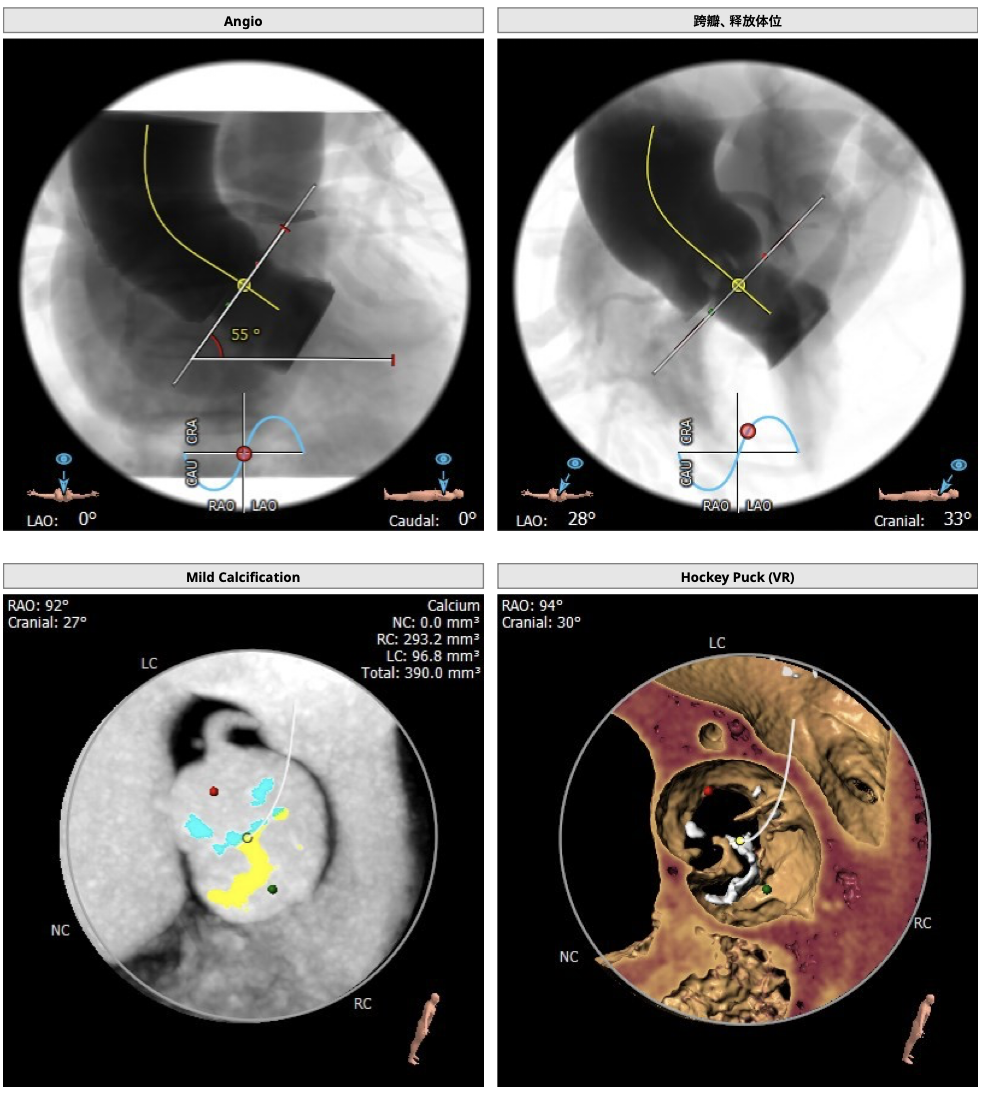

主动脉CT

患者为TYPE0型二叶瓣,轻中度钙化,瓣叶可见增厚,冠脉高度可,法式窦结构大,左室大小尚可,心肌肥厚,升主动脉可见增宽。

经分析研判,结合患者瓣上结构,拟采取downsize手术策略,优先选用L26号的VenusA-Valve瓣膜,备L23,使用VenusA-Plus确保瓣膜的精确释放,减少瓣膜移位风险,瓣膜释放后结合造影和超声情况,决定是否后扩。